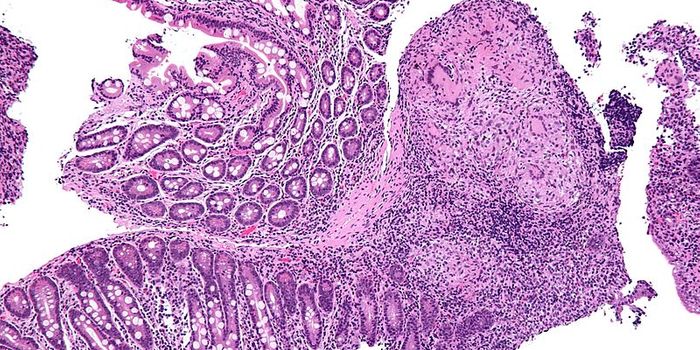

FEB 06, 2017ImmunologyThe recent discovery of not just one, but multiple genes that fail to protect the gastrointestinal (GI) tract from infla ...